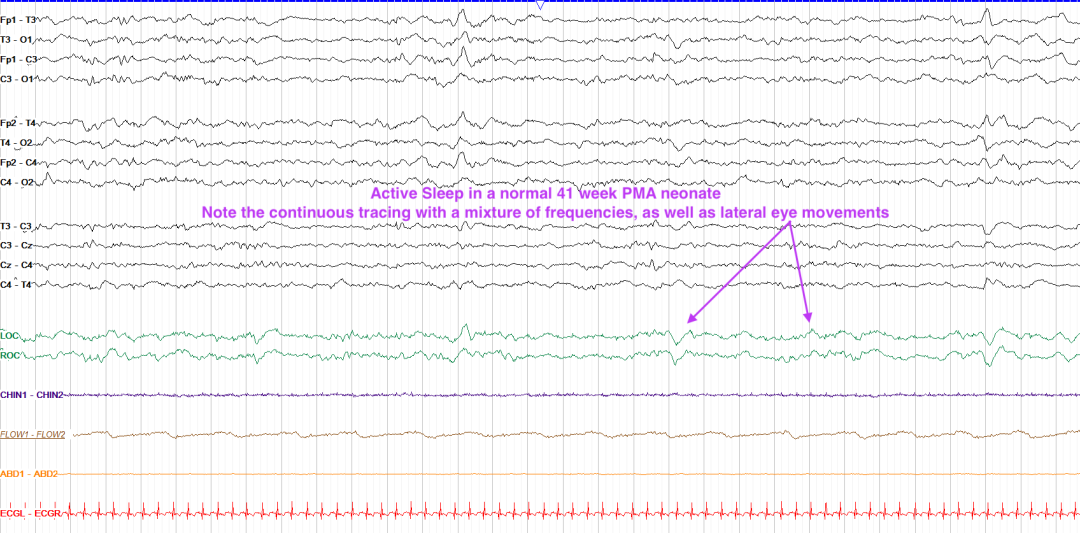

29周后:分三态:清醒(Awake)、活跃睡眠(Active Sleep)、安静睡眠(Quiet Sleep)。

活跃睡眠(类似成人REM):闭眼、眼球运动、不规则呼吸,30-36周以θ-δ波为主,38周后混合快波。